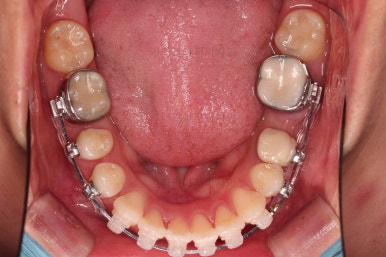

마찬가지로 초진 시 입안의 모습입니다.

입안 사진을 보니 문제점이 보이죠.

바로 어금니가 없는 상태였습니다.

장치를 부착해서 가지런하게 하고요.

발치가 필요한 치아를 하나씩 뽑아나갑니다.

어금니 발치 공간이 어마어마하게 넓죠?

이번 부산사랑니교정 환자분이 선택하신 장치는 데이몬 클리어라고 하는 자가결찰 세라믹 장치인데요.

현존하는 세라믹 장치 중에 가장 심미적인 장치입니다.

철사를 잡아주는 뚜껑은 금속으로 되어있는 클리피씨나 엠파워 클리어에 비해 뚜껑까지도 세라믹으로 되어있기 때문이죠.